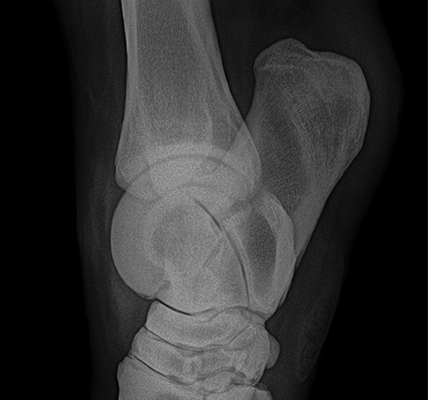

Diagnóstico por imagen